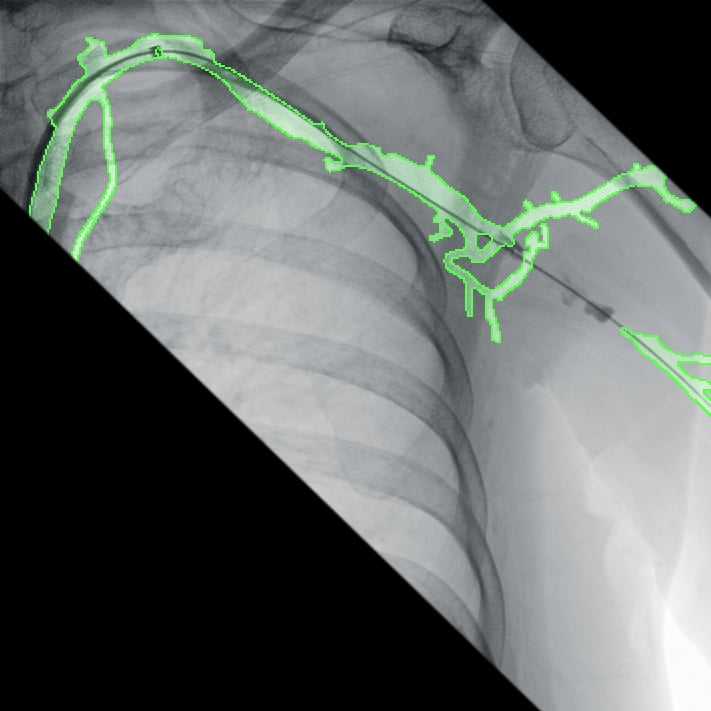

Полное отсутствие искажений снимков в сочетании с высоким динамическим диапазоном широко востребованы как при сложных операциях в нейрохирургии, сосудистой хирургии, инвазивной радиологии, так и в гибридных областях применения, а также в ортопедии, травматологии. В сосудистой хирургии особенно важны высокий динамический диапазон и пространственное разрешение, обеспечивающие детальную визуализацию даже мельчайших сосудов. Специализированное программное обеспечение SmartVascular позволяет проводить настройку системы для васкулярных операций и сосудистой хирургии.

Точная визуализация анатомических деталей, мягких тканей и костных структур обеспечивается за счет светочувствительной матрицы 3kх3k пикселей с высоким динамическим диапазоном.

- программный пакет для сосудистой хирургии,

- субтракционная ангиография с применением СО2.